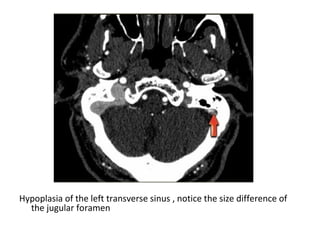

c) Diagnostic Difficulties :

-Diagnostic difficulties arise with congenital

variations of the venous system (i.e. normal

hypoplasia of the transverse sinuses) ,

arachnoid granulations and normal slow

turbulent flow

Hypoplasia of the left transverse sinus , notice the size difference of

the jugular foramen

Transverse MIP of phase-contrast images, to differentiate whether there is a

hypoplastic transverse sinus or thrombosed sinus , you need to look at the

source images, on the source image on the right you can see that there is

no hypoplasia (blue arrow), in this case there thrombosis of the left

transverse sinus